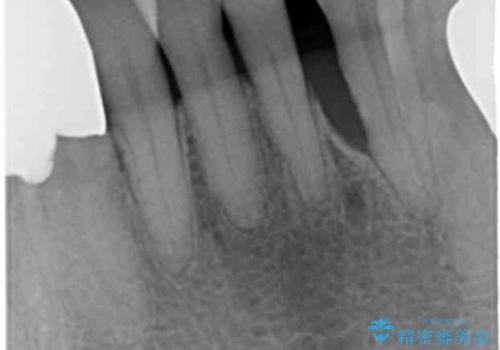

精査したところ、前歯の咬み合わせが反対になっていること、下の奥歯(下顎両側67)が4本欠損していることから動揺が生じていました。

入れ歯も抵抗があるとのことから、相談を重ね、今の状態では保存不可能な下の前歯(左下2)を抜去し、ブリッジや連結補綴により動揺を抑えることにしました。

下顎大臼歯が欠損したままで今ある歯に負担がかかりやすいことから、長期的予後は保証できないことをご理解頂いた上で治療を行いました。